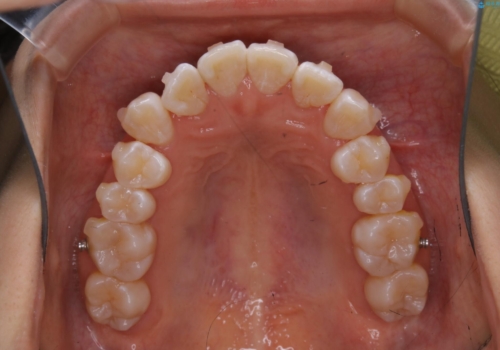

前歯のがたつきとオープンバイト:インビザラインでまとめて治す

- 噛み合わせと、前歯のがたつきが気になるとご相談にいらした方です。インビザラインFULLで綺麗な歯並びと噛み合わせを作ることが出来ました。

オープンバイトの方への治療は、通常抜歯を行いワイヤーによる矯正治療を行うことが多いですが、今回はインビザラインの特性を生かし、非抜歯にて綺麗な歯並びを作ることが出来ました。